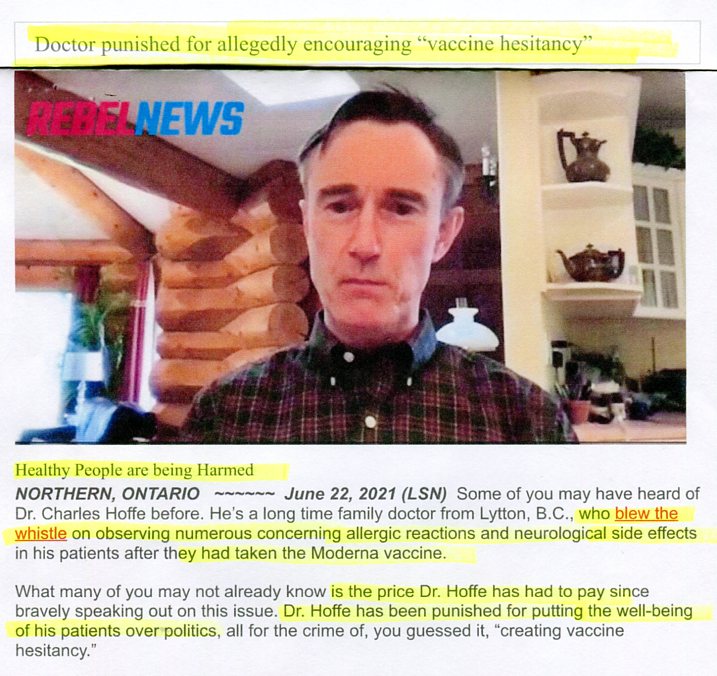

Science shows COVID vaccines cause blood clots

watch JUST SAY NO TO THE CLOT SHOT Hoffe

Doc Hoffe under investigation by College of Physicians

(promoting vaccine hesitancy by warning of vax clots)

Justice Centre defends Doc Hoffe free speech

COVID vaxxers Satanic attack on Godsend doc Hoffe

watch Whistle blowing doc encouraging vaccine hesitancy

listen RFKjr INTERVIEW CANADA COVID DOC HERO

(using coercion to experiment on humans without consent)

News/Defender, June 2021

watch Doc describes escaping fire destroying his clinic

(how mRNA vaccines cause blood clots/heart failure)

UPDATE: Doctor Hoffe is safe...

R U SAFE COVID HERO DOC HOFFE?

(no news of Lytton doc since fire June 30)